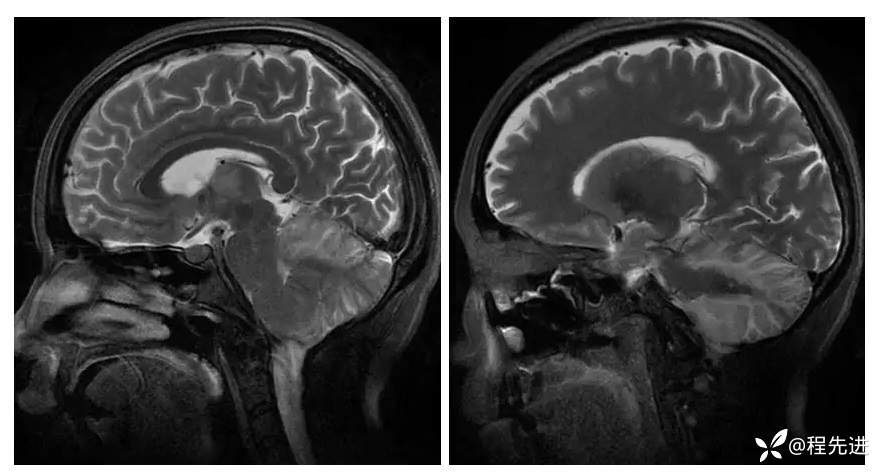

【现病史及既往史】:孕期38周,蛋白尿10天,血压升高6天,剖腹产后一天出现头晕,头痛,嗜睡。既往糖尿病史

查体:不配合,血压波动,130-157/85-109mmHg

影像检查: